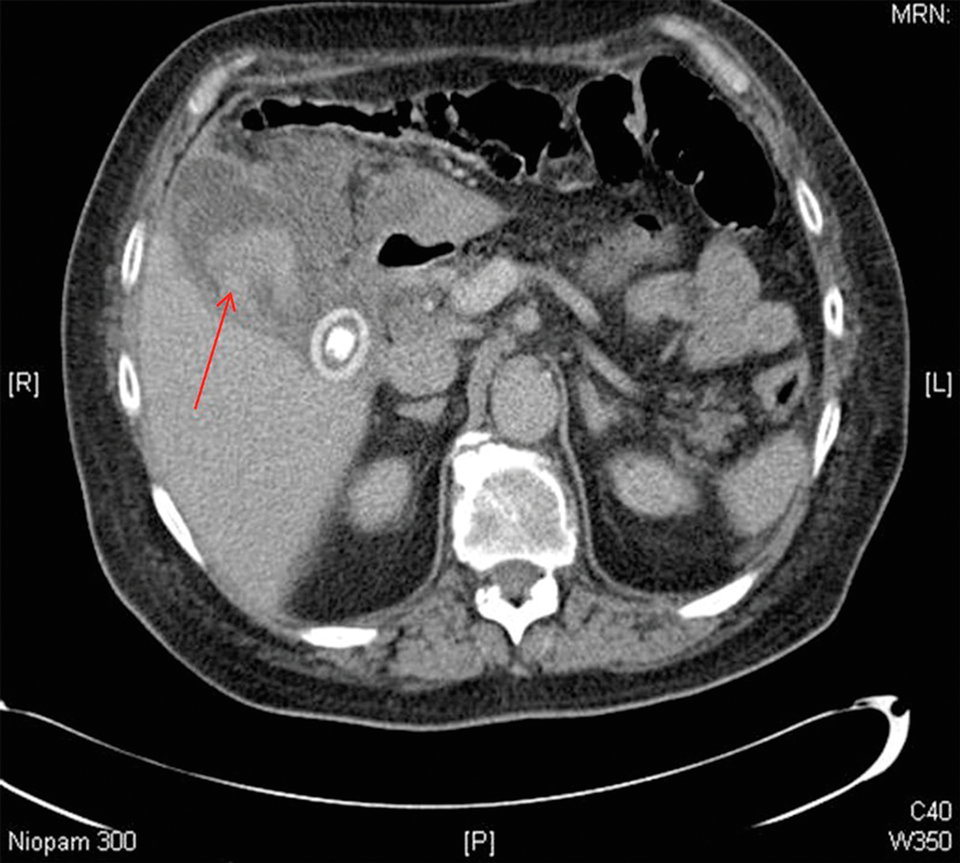

Eine hämorrhagische Gallenblasenentzündung zu erkennen, ist nicht trivial, erklären Munir­ Tarazi­ vom Department of General Surgery des Tunbridge Wells Hospital im englischen Tunbridge Wells und seine Kollegen. So sind die Symptome auf den ersten Blick häufig irreführend und die Cholezystitis mit klassischen bildgebenden Verfahren oft nur schlecht darzustellen. Im CT lässt sich die ggf. verdickte Wand der geblähten Gallenblase erkennen und das Blut im Inneren wird als heterogene Masse sichtbar. Im Ultraschall erscheint das Blut als echoreiche Region.

Es ist nicht die Leber, die blutet: Die Hämorrhage befindet sich in der geblähten Gallenblase und ist als heterogene Masse zu erkennen. Zusätzlich sind Wandverdickungen auf dem CT sichtbar (roter Pfeil). Es ist nicht die Leber, die blutet: Die Hämorrhage befindet sich in der geblähten Gallenblase und ist als heterogene Masse zu erkennen. Zusätzlich sind Wandverdickungen auf dem CT sichtbar (roter Pfeil). © Tarazi M et al. J Surg Case Rep 2019: rjy360